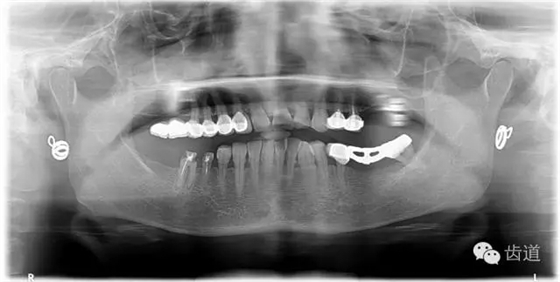

1、術(shù)前全景片

1、治療前